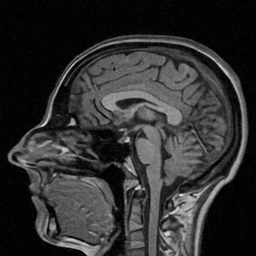

| Ground Truth (PSNR) | Zero-filling (22.33) | TV (25.22) | SIDWT (25.10) | PBDW (27.39) | |

| PANO (28.77) | FDLCP (29.78) | ADMM-Net (27.91) | BM3D-MRI (29.35) | Ours (30.48) |

First, we test on 25 T1-weighted MRI data using three different undersampling patterns with a fixed 10% sampling rate. Fig. 3 shows the quantitative results (PSNR). Our method performances best for all three cases and has stronger stability compared with the second best method on variance. As for the effect of sampling ratios variation, we use radial mask under 10%, 30% and 50% sampling rates with evaluation of RLNE and MSE. Fig. 4 shows that our method has the lowest reconstruction error for all sampling rates. For more intuitive comparison, we illustrate the reconstruction error in term of pixels in Fig. 5. We also offer the qualitative comparison in Fig. 6. Visualized results demonstrate our method has better performance in both artifacts removing and details restoration. Time consuming is also considered. We compare our method with others on the 25 T1-weighted data using Radial mask with 10% and 50% sampling rate. Notice that ADMM-Net and ours are tested on GPU for the incorporation of deep architecture. Tab. 1 shows that our method provides an efficient reconstruction process and comes to the fastest method among the state-of-the-art competitors.